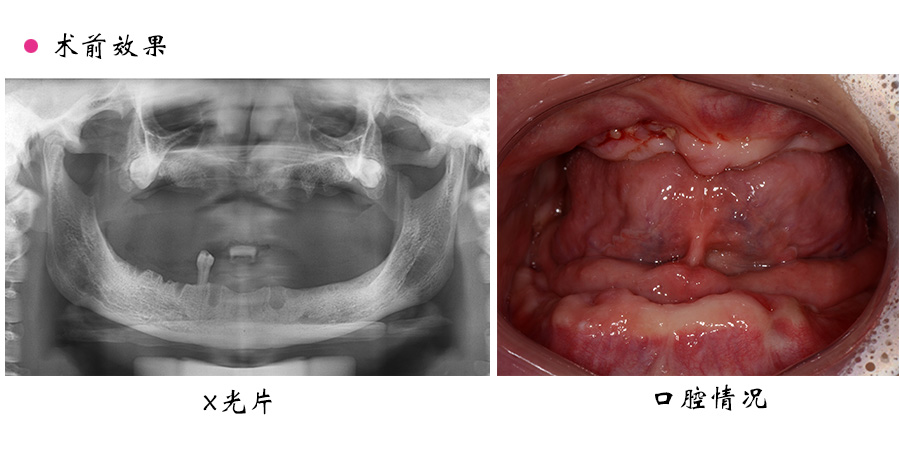

姓名:蒋女士

性别:女

年龄:45岁

牙齿问题:上下颌全口缺失

治疗方案:上颌种植覆盖义齿修复,下颌活动义齿修复

蒋女士年纪不算大,但是牙齿已经全部掉光了,来医院检查时,医生检查了她的口腔状况,感到非常遗憾和惋惜。不到五十岁牙齿就掉光了。

通过全面的检查诊断与分析后,医生给蒋女士制定了上颌种植覆盖义齿修复,下颌用活动义齿修复的方案。